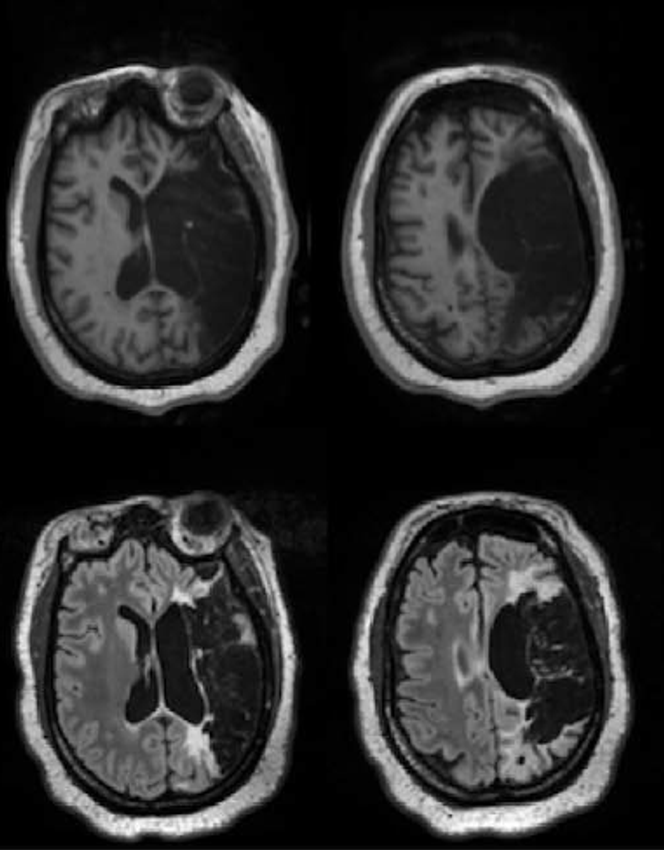

Les mois passent, puis les années. Lorsque cette patiente est réévaluée cinq ans plus tard, soit 61 mois après son AVC, les images de l’IRM cérébrale sont sans appel : une zone de 432 cm³ est détruite, soit une portion très importante du volume d’un cerveau humain, estimé à environ 1 100 cm³ chez la femme. L’encéphalomalacie, littéralement le ramollissement cérébral, touche les régions frontale, temporale et pariétale gauches et correspond aux territoires de l’artère cérébrale moyenne et de la portion postérieure de l’artère cérébrale antérieure.

Son score NIHSS est alors de 10. Elle présente une hémiplégie droite, une perte de sensibilité du même côté et une hémianopsie droite, c’est-à-dire une amputation de la moitié droite du champ visuel.